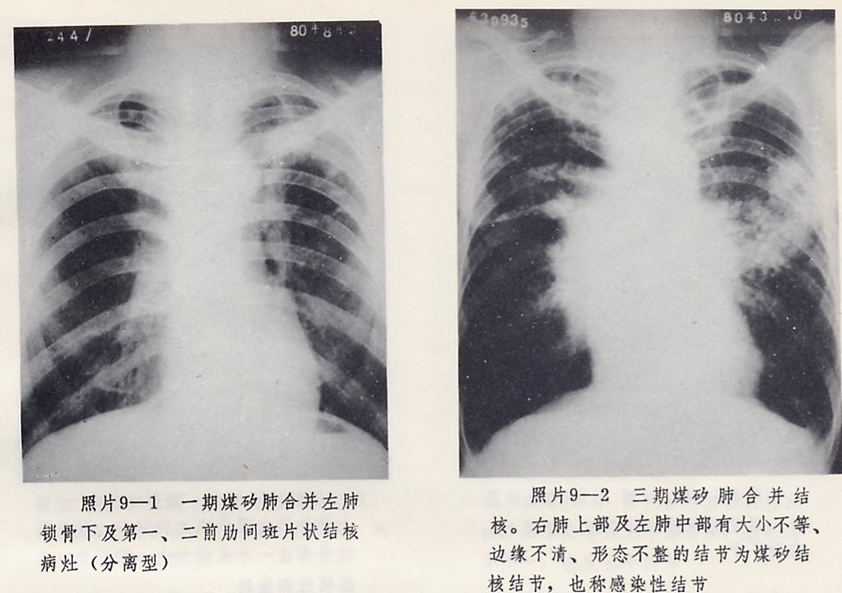

矽肺结核的病理特点是既有矽肺又有结核病变。镜下观,中心为干酪样坏死物,在其边缘有数量不多的淋巴细胞、上皮样细胞和不典型的结核巨细胞,外层为环形排列的多层胶原纤维和粉尘。也可见到以纤维团为结节的核心,外周为干酪样坏死物和结核性肉芽组织。坏死物中可见大量胆固醇结晶和钙盐颗粒,多见于矽肺结核空洞,呈岩洞状,壁厚不规则。

2.并发症:矽肺常见并发症有肺结核、肺及支气管感染、自发性气胸、肺心病等。一旦出现并发症,病情进展加剧,甚至死亡。其中,最为常见和危害最大的是肺结核。矽肺如果合并肺结核,矽肺的病情恶化,结核难以控制,矽肺合并肺结核是患者死亡的最常见原因。